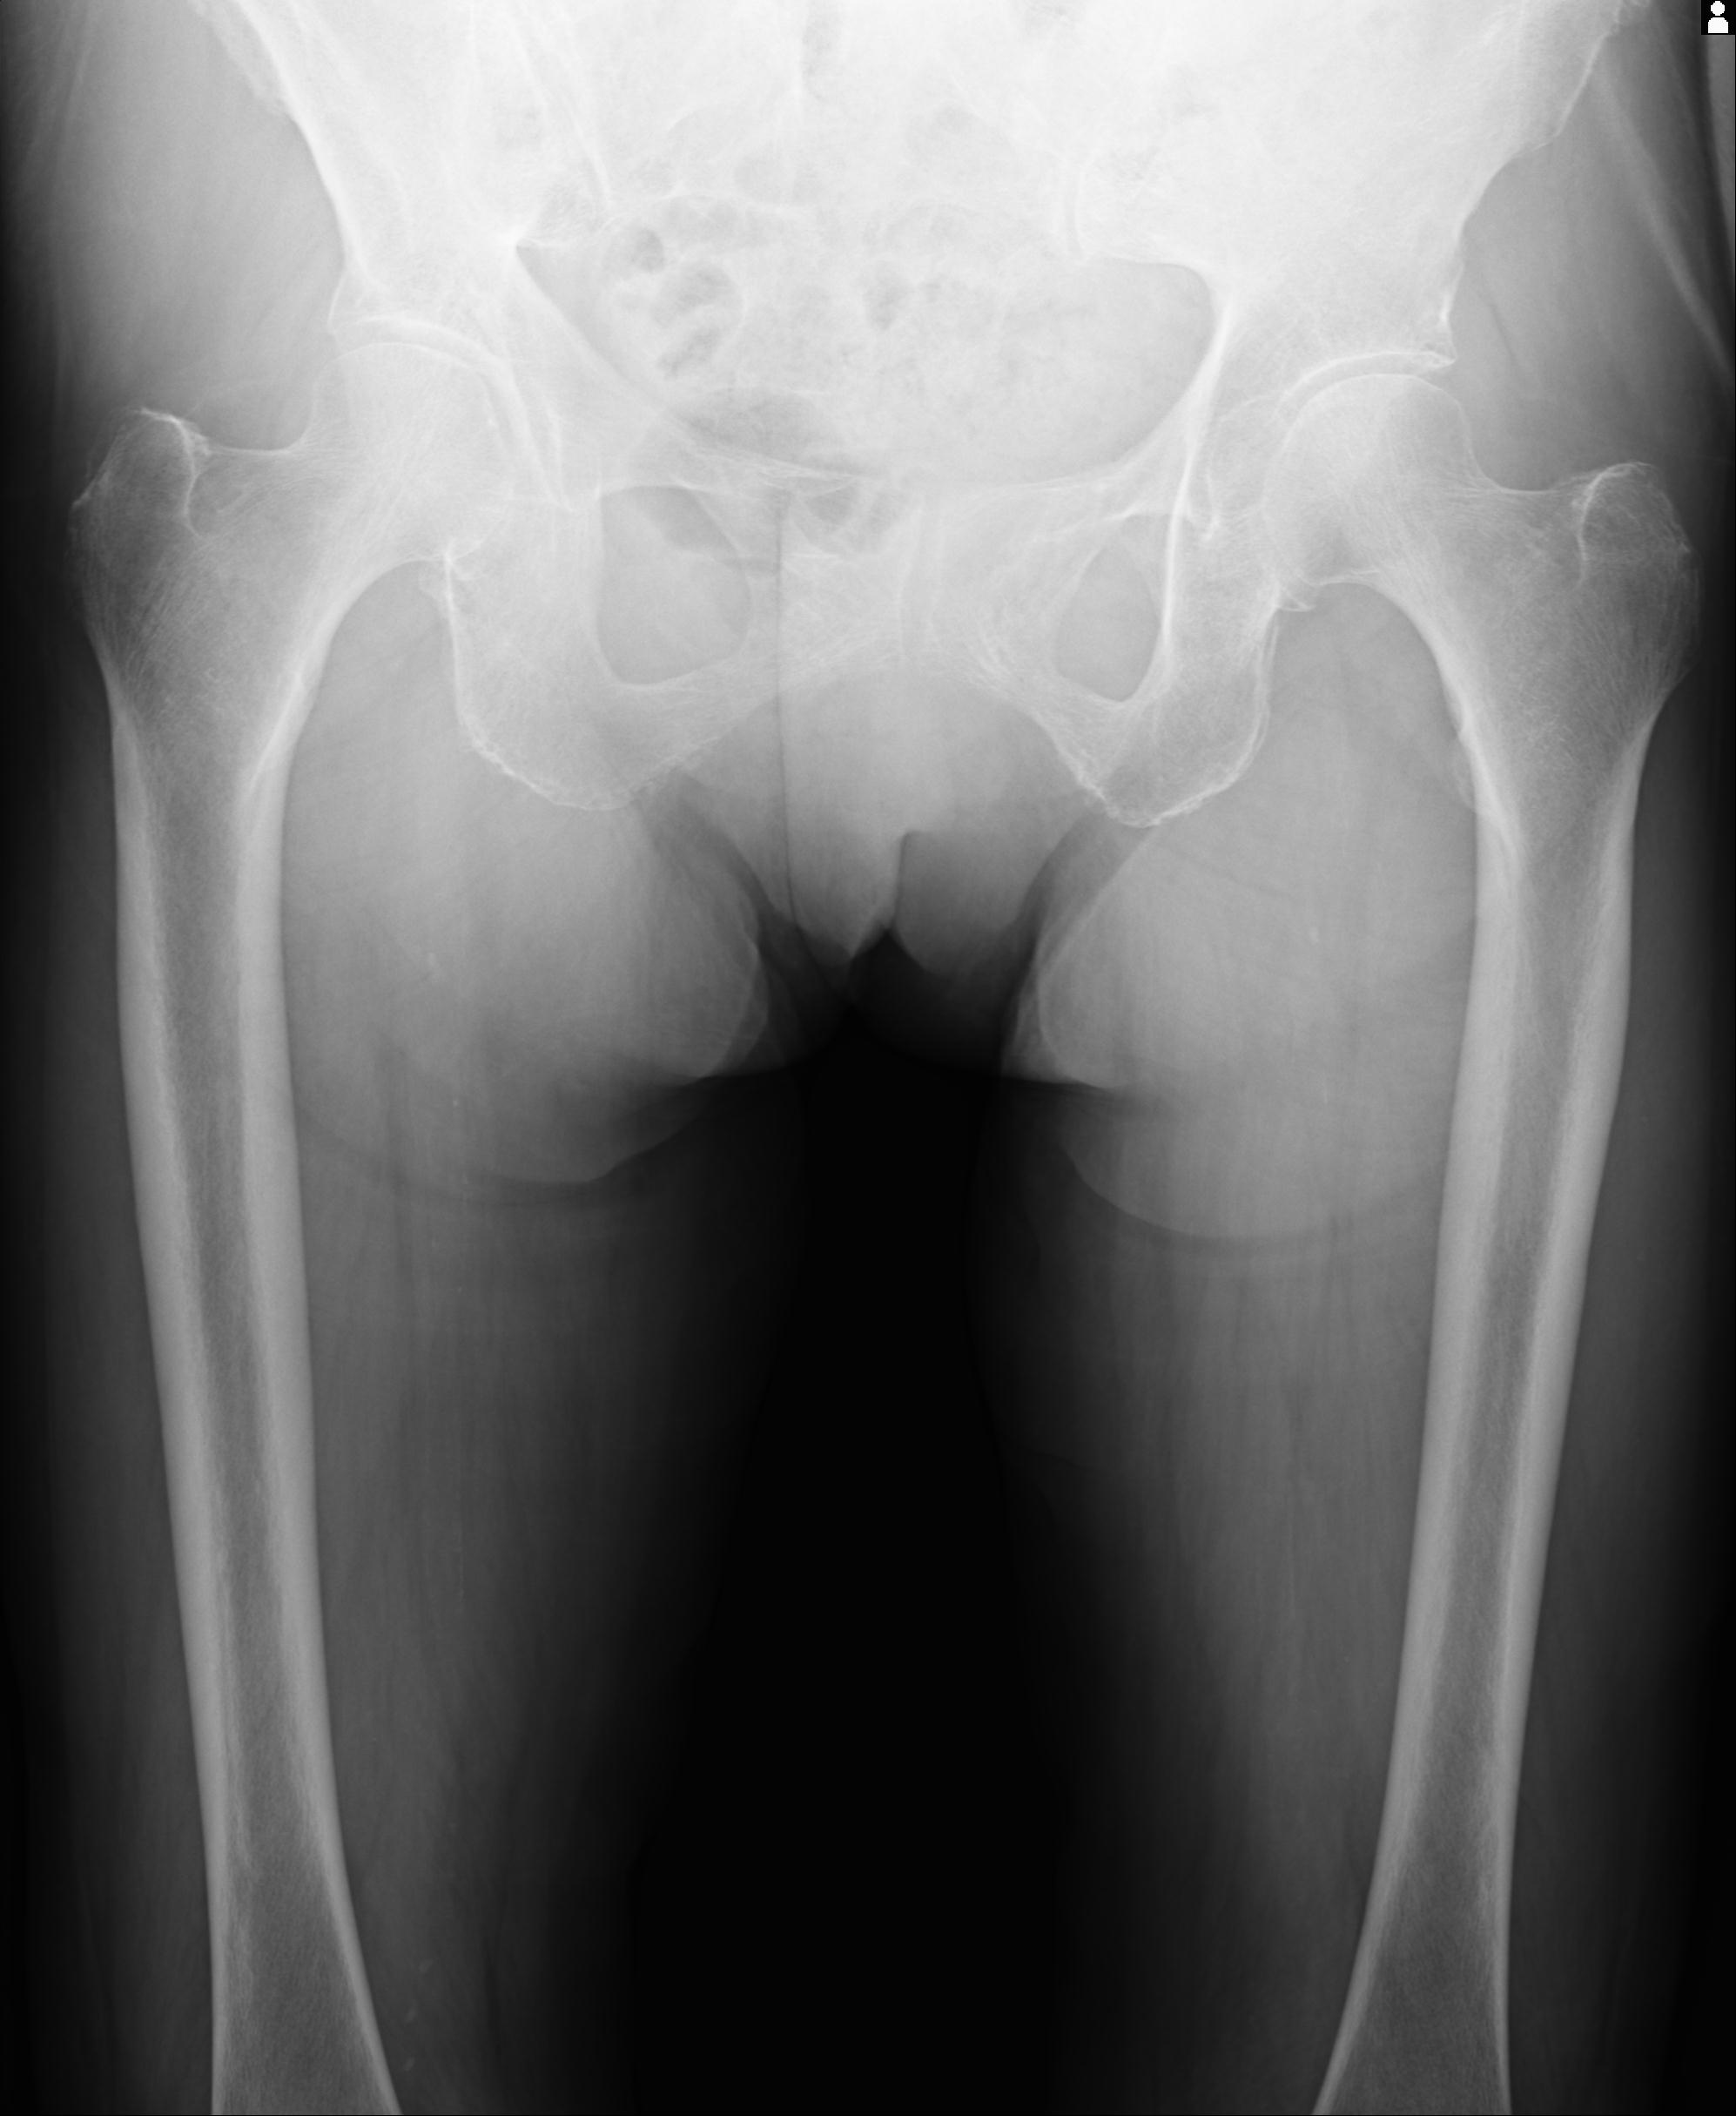

100703 1/27 両股正面+軸 1/29 両股正面+軸 94歳女性 パンソンロン

46666 1/28 両股正面+軸と 1/26 右手関節 2R 76歳女性 右転子部骨折

37 1/18 両股正面+軸 1/22 2R 86歳女性 右転子下

91569 3/25 両股正面とラウエン 70歳女性 人工骨頭+バンクーバー